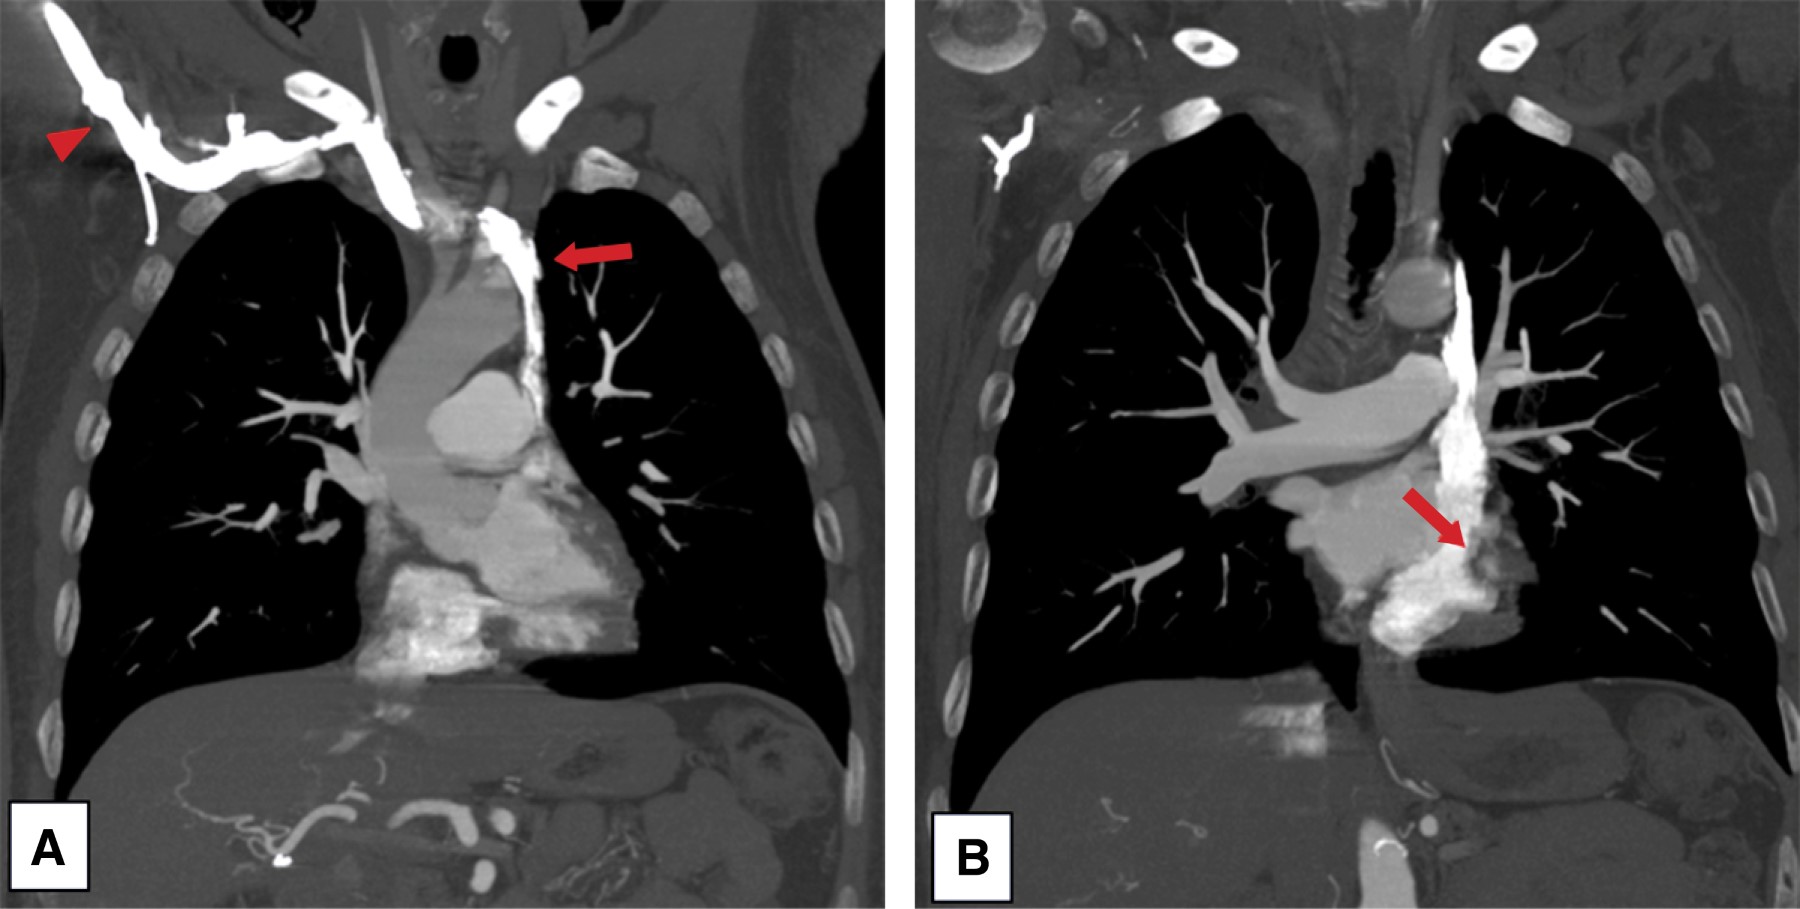

Pacemaker implantation through the persistent left superior vena cava due to the absence of the right superior vena cava. Report of a case

Introduction: the persistence of the left superior vena cava (PLSVC) has a prevalence of 0.21% in the general population. Case presentation: 67-year-old male diagnosed with third-degree AV block, requiring pacemaker placement. However, due to the absence of a right superior vena cava, corroborated by CT angiography, a definitive pacemaker was placed through a persistent left superior vena cava. Conclusion: the persistence of the left superior vena cava (PLSVC) is the most common thoracic venous anomaly. It can cause a number of clinically significant symptoms, even in a heart with normal anatomy. Pacemaker placement makes electrode fixation difficult due to tortuous travel.

Figure 1